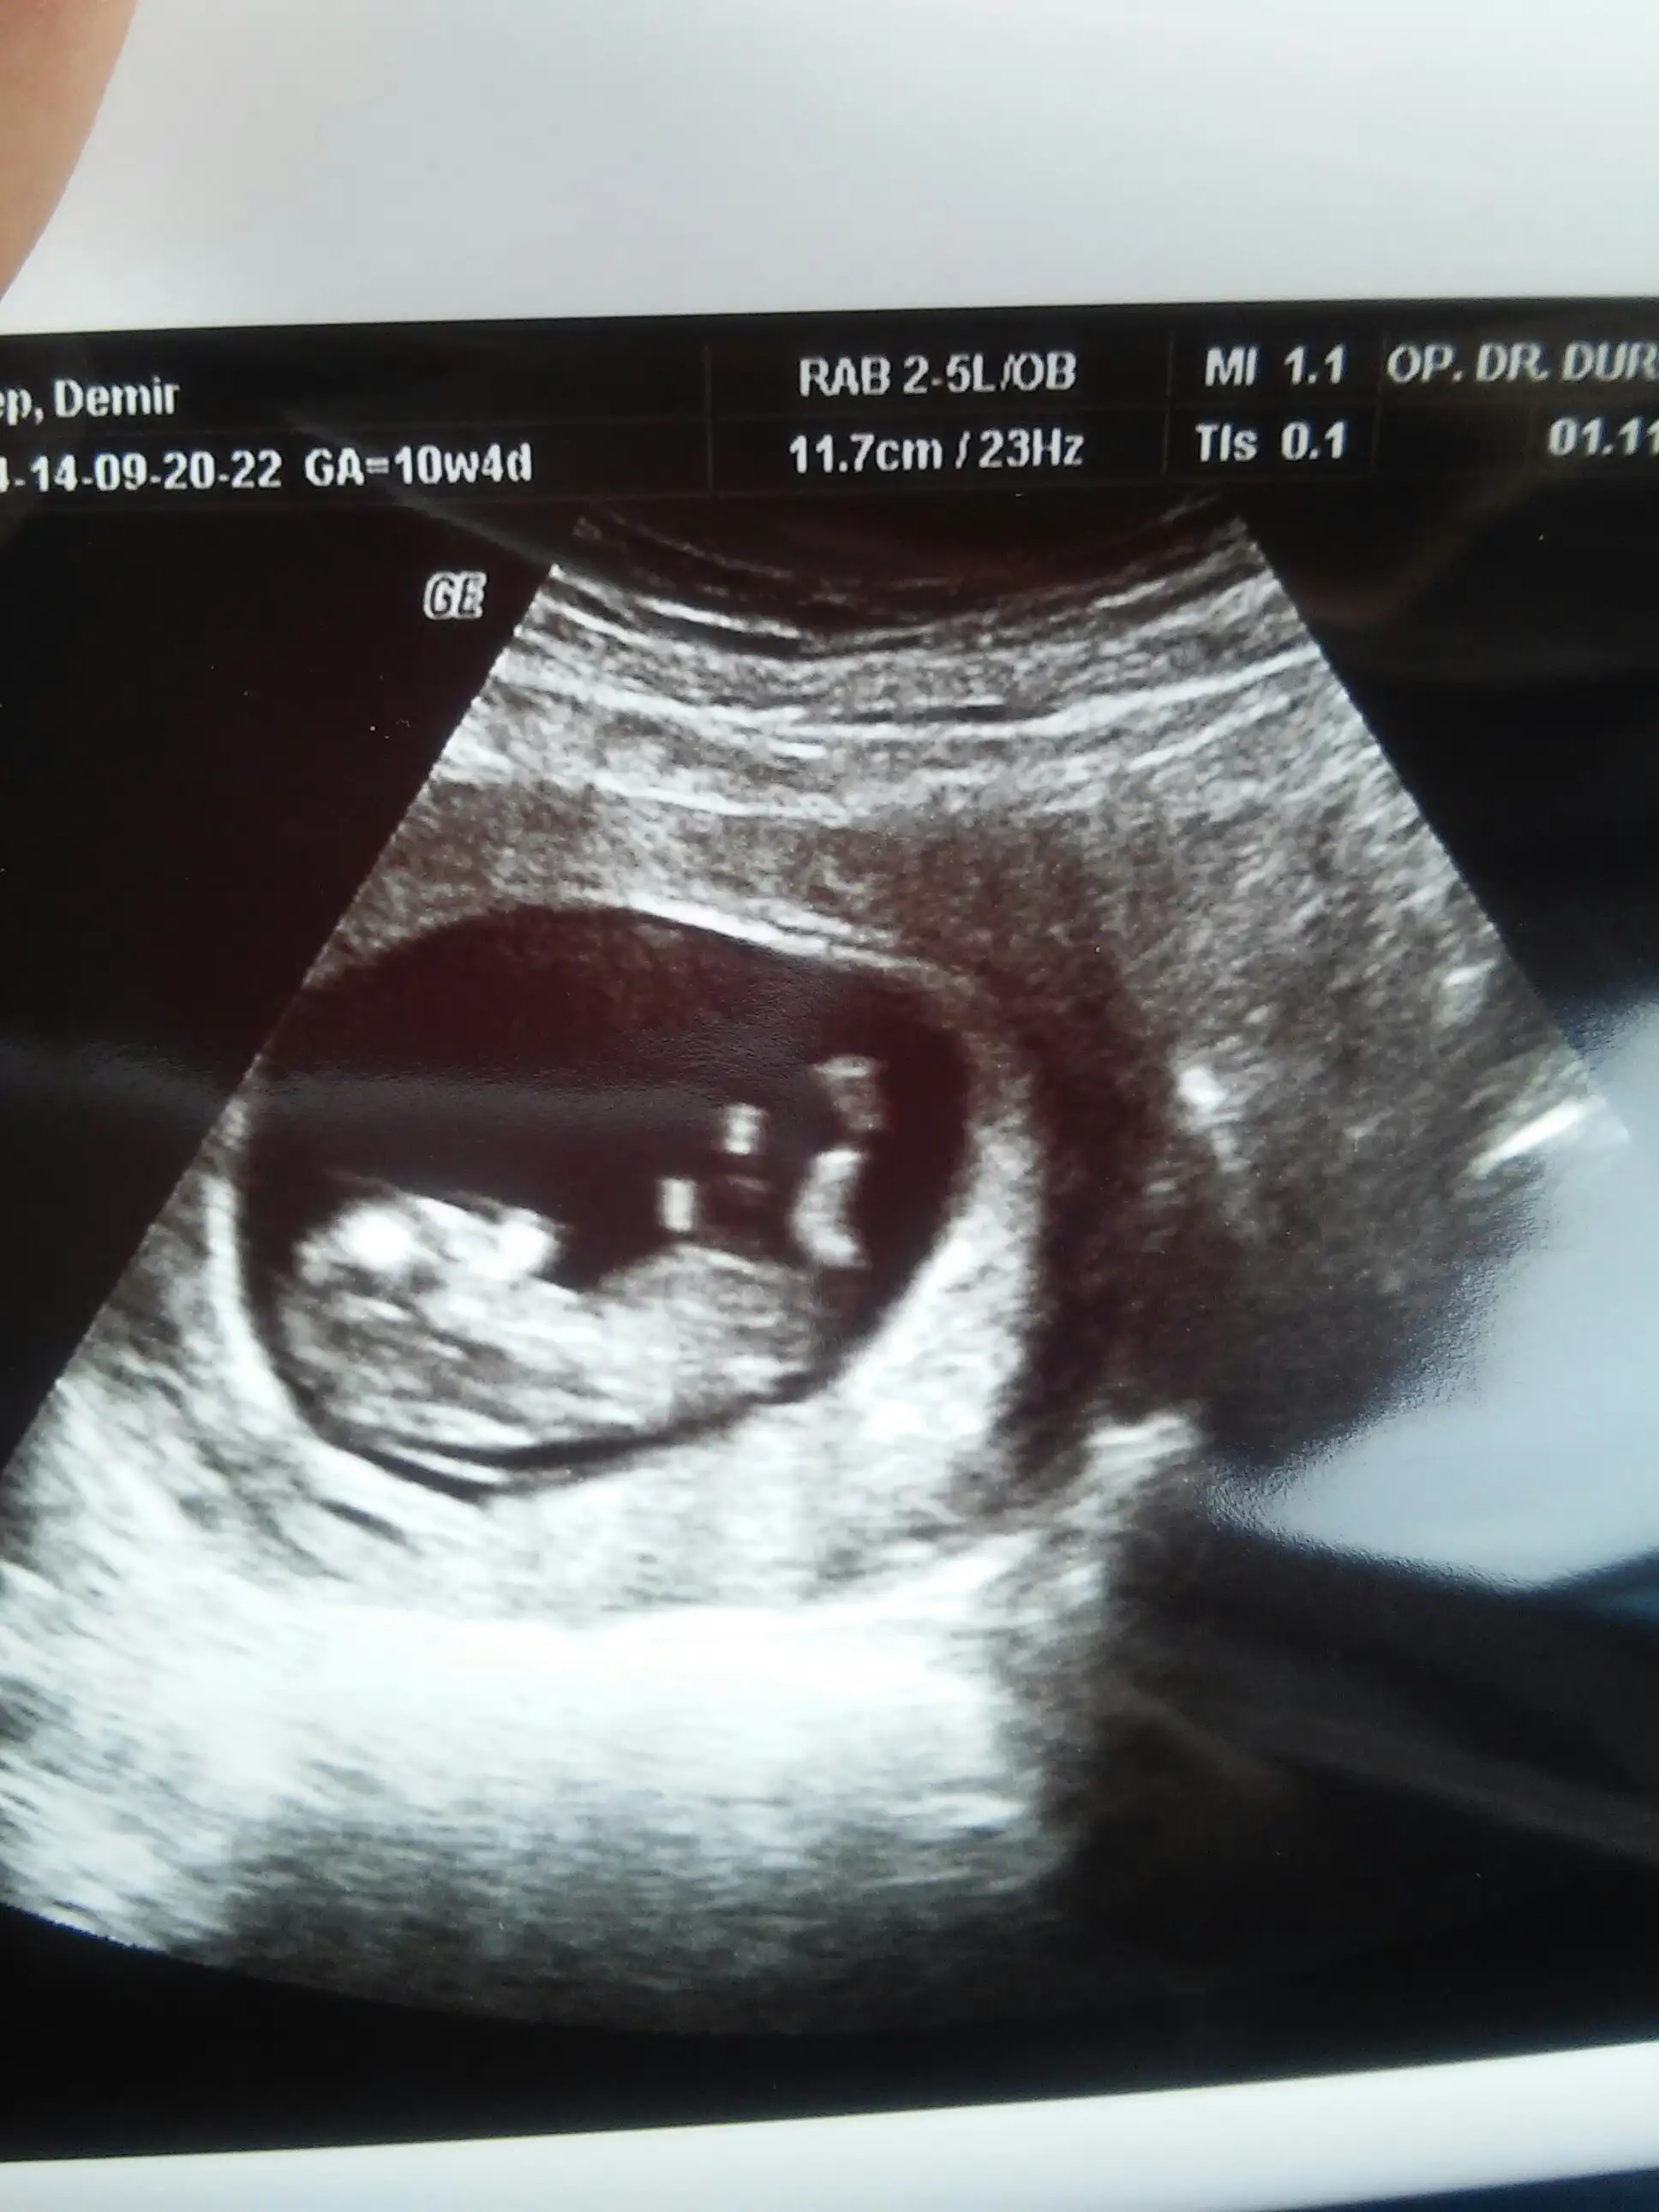

kızMerhabalar,lutfen benim bebisimide tahmin edermisiniz??? 11 haftaligiz,rabbim herkezin gonlune hayirlisini nasip etsin

Tamam canim. Haftaya 12 haftalik fotosunu atarim doktora gitcem :) tesekkur ederim. Evet ilk bebegim o yuzden coookk merak ediyorum :) Rabbim hayirlisini versin de kiz erkek hic farketmez. Ama bu merak yok mu :)) mutlaka yazarim ogrenincede :)Zeyyal bebek on haftalikmis daha senin nub icin erken zaten 12haftalik fotosuna bakarız ınş ozaman daha doğru bişey deriz sen benim şimdiki yorumumabakma çünkü nub bu haftadan sonra acı alır yeni foto bekliyoruz